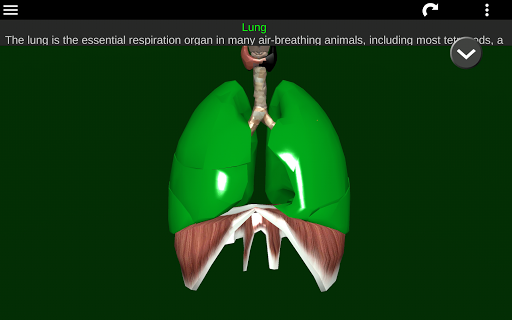

* Sistem pernafasan, yang meliputi trakea, bronkus, paru-paru dan animasi sistem ini.